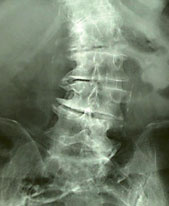

Abb. 4

Arthrose der Wirbelsäule, hier mit deutlicher Fehlform (Skoliose).

Degenerativer Rheumatismus: Arthrosen der Gelenke oder der Wirbelsäule sind Krankheiten durch Schäden am Knorpel und an anderen Gelenkstrukturen. (Abb. 1 und 4) Die Ursache bleibt meist unbekannt. Fehl- oder Überbelastung, Entzündungen oder Stoffwechselstörungen sind jedoch wesentliche Faktoren.